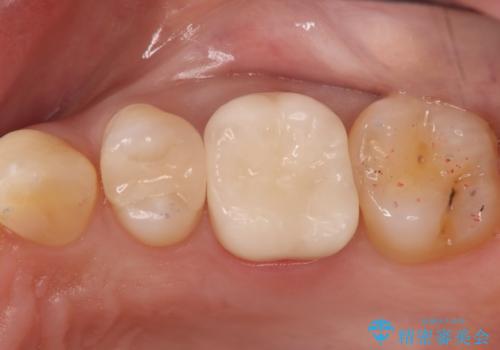

銀の詰め物が外れた。プラチナゴールドインレー

適合の良い修復を希望されましたので、プラチナゴールドインレーにて治療を行っております。

PGA(プラチナゴールド)インレーは適合もよく、壊れるリスクも極めて少ない修復です。

- インレーおよびクラウンは脱離するリスクがあります

- 形成量はセラミックより少ないですが、歯の形成、修復後に歯に症状が出ることがあります